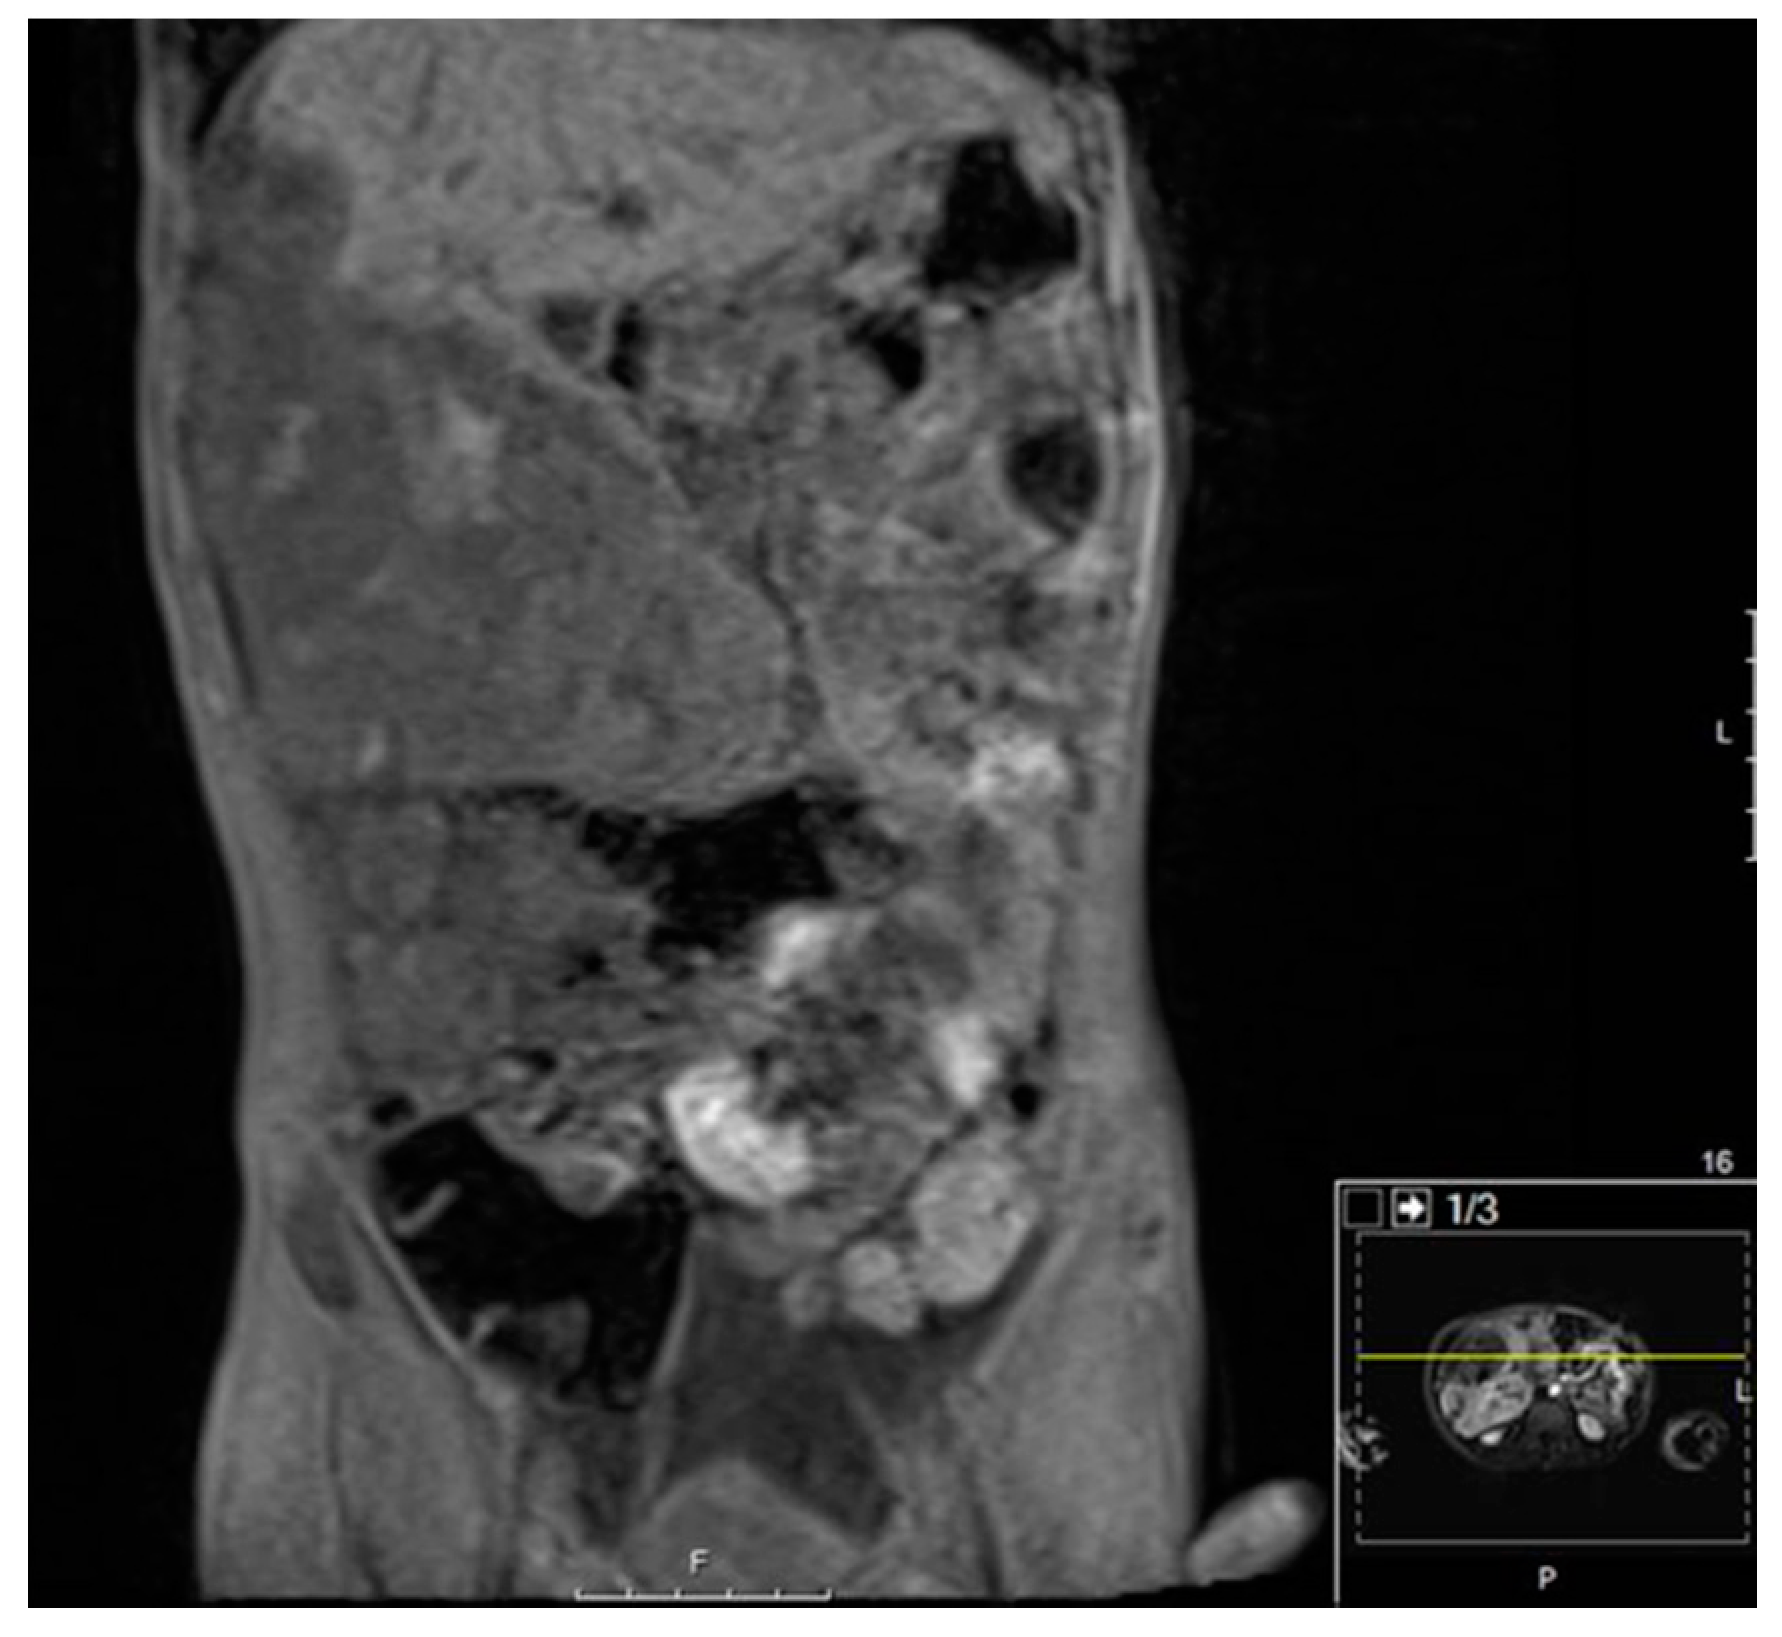

5.2.4. Diagnostic Imaging